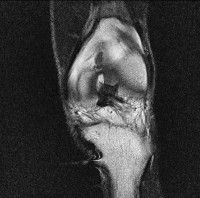

무릎 mri 간단히 봐주실 수 있으시나요 ㅠㅠ

안녕하세요 8년전 십자인대 수술하고 최근 무리한 운동에 무릎 불편감이 생겨서

mri 찍었습니다.

진단결과는 첫 찍은 병원에서 활액막염 이라는 진단을 받았습니다. 혹시 봐주실 수 있으실까요?

진단결과가 달라 혼란스럽습니다 ㅠㅠ

• 안녕하세요. 강성주 의사입니다.

올라온 MRI가 단편적이라서 정확한 진단에 어려움이 있지만 십자인대에는 큰 이상이 있지는 않은것 같으며, 무릎관절내 물이 있는 것으로 보아 활액막염의 진단이 맞을 것 같습니다.

하지만 단편적인 영상이기 때문에 촬영병원에서 정확한 판독지 등을 받으시는 것이 좋겠습니다.